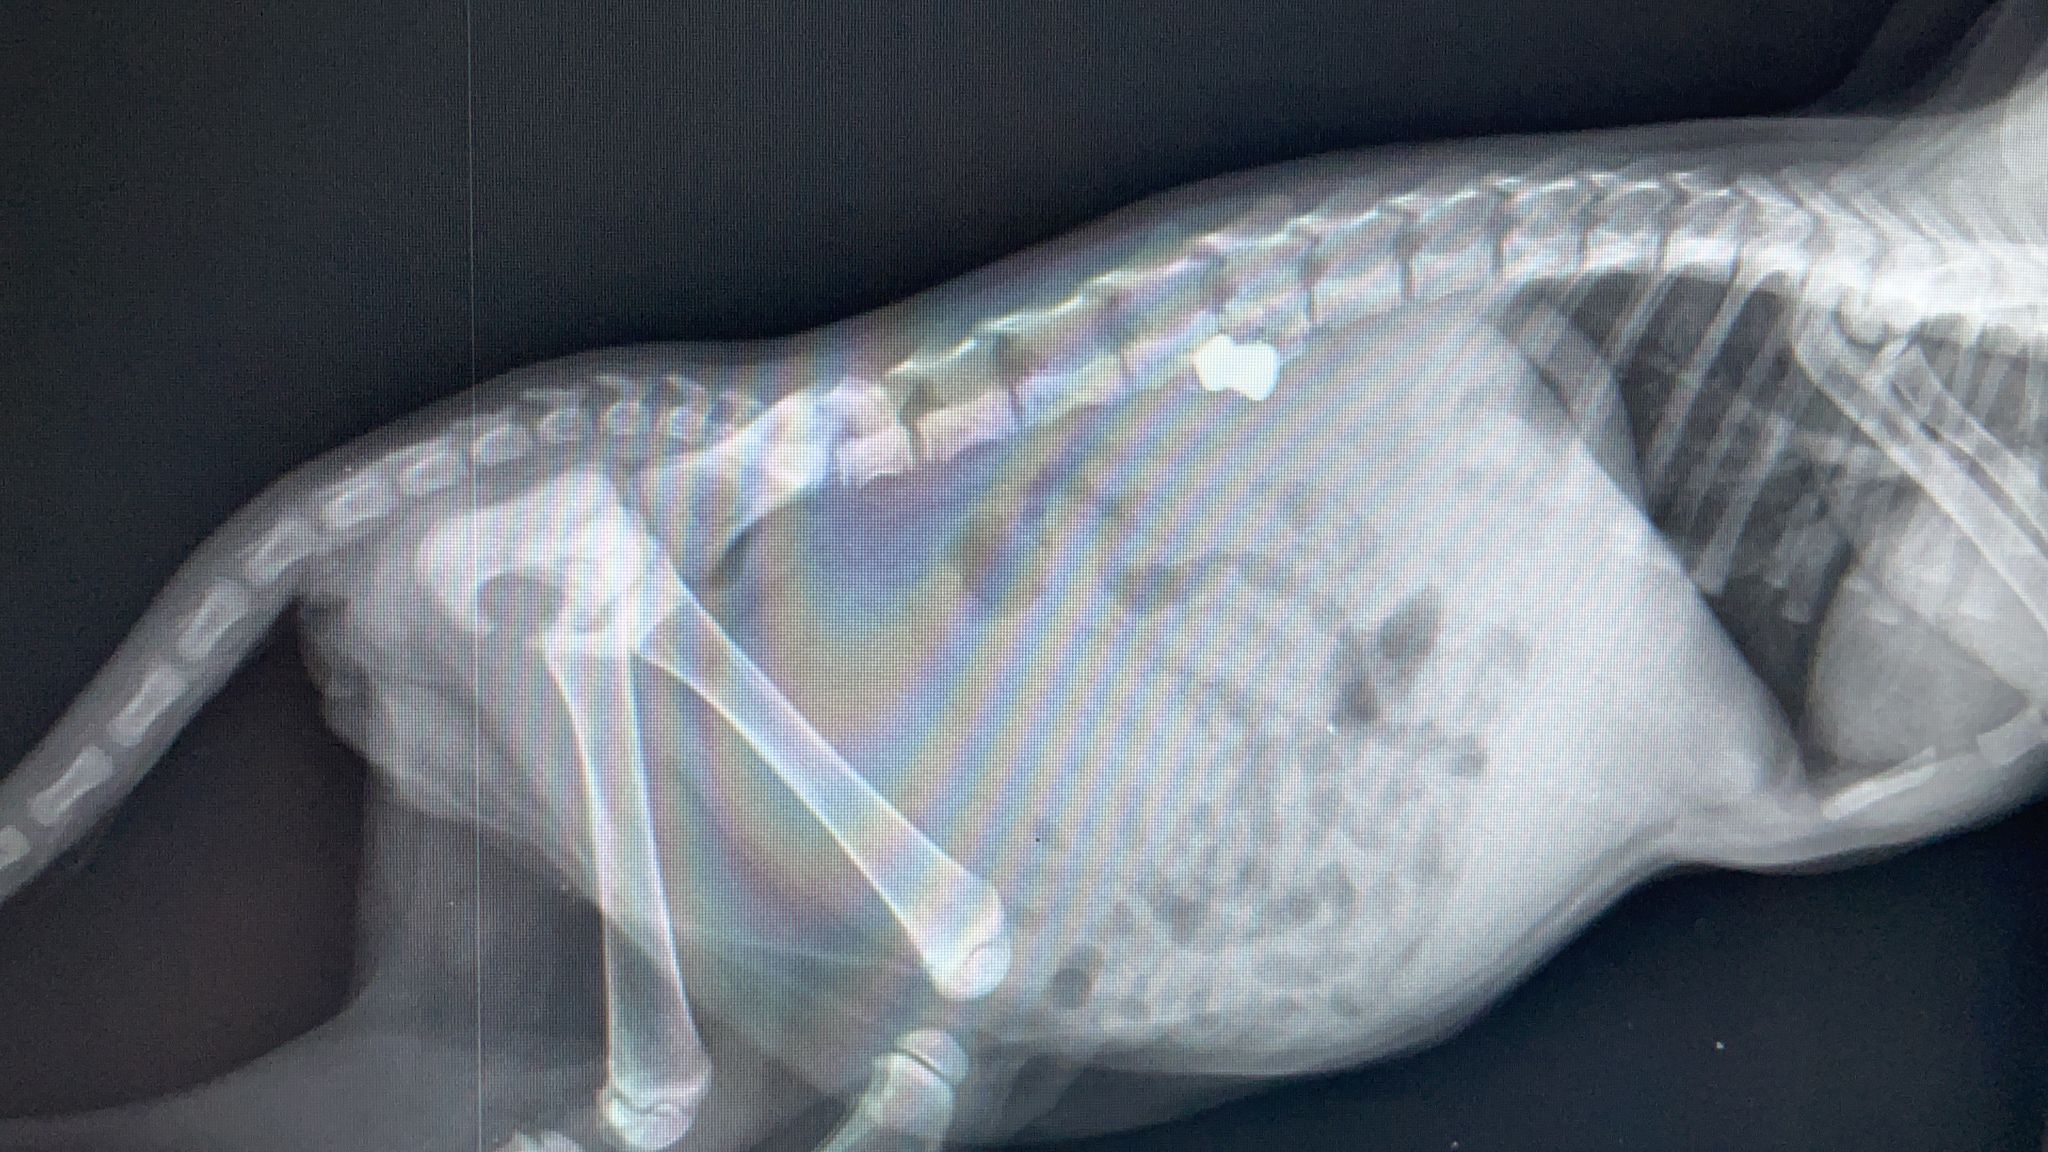

La legge del più forte si applica in natura per la sopravvivenza della specie: il più forte uccide il più debole per sfamarsi. Ma questo è un atto di crudeltà, un atto che non ha motivo di esistere e sussistere: una gattina è stata fucilata alla schiena per puro divertimento. È successo a Castellammare, la polizia municipale ha trovato la micina intrappolata nella griglia anteriore di un’auto, dove probabilmente si era rifugiata per sfuggire alla cattiveria di qualcuno. La gattina (di qualche mese di vita) aveva difficoltà a muoversi: un uomo l'ha sentita miagolare dentro ad una macchina nel quartiere “case nuove” e lo ha segnalato alla polizia municipale. Ed ecco il pronto intervento con le cure di un veterinario. La gattina è stata colpita con un fucile ad aria compressa e dopo la rimozione del pallino e le cure, non è più in pericolo di vita: ora è in mani sicure perché già affidata alle attenzioni di alcuni volontari.Pietro Vultaggio